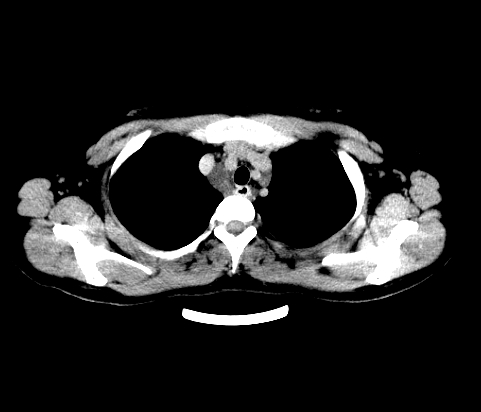

胸部